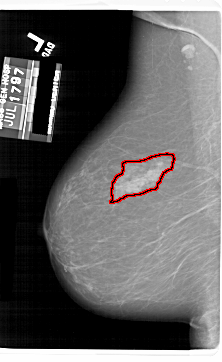

A_1802_1.LEFT_CC

LEFT_CC LINES 5956 PIXELS_PER_LINE 3901 BITS_PER_PIXEL 12 RESOLUTION 43.5 OVERLAY

FILE: A_1802_1.LEFT_MLO.OVERLAY

TOTAL_ABNORMALITIES 1

ABNORMALITY 1

LESION_TYPE MASS SHAPE ASYMMETRIC_BREAST_TISSUE MARGINS ILL_DEFINED

ASSESSMENT 4

SUBTLETY 5

PATHOLOGY BENIGN

TOTAL_OUTLINES 1

BOUNDARY

FILE: A_1802_1.LEFT_CC.OVERLAY